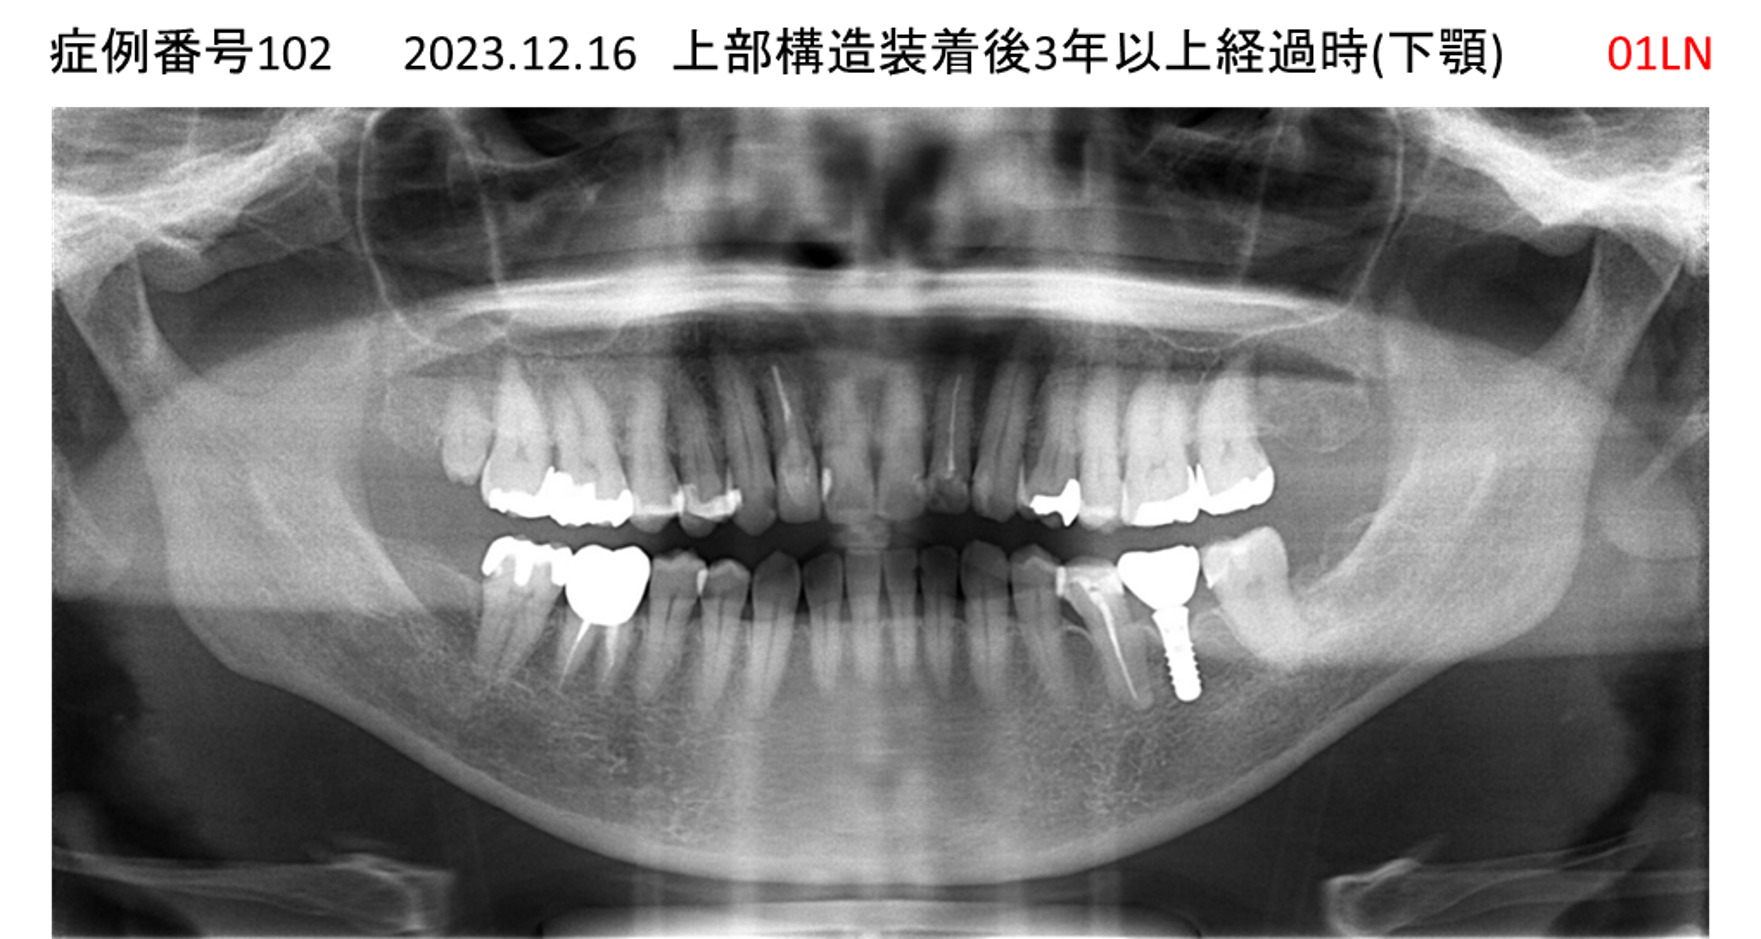

奥歯で噛めない患者様のインプラント症例

| 治療名称 |

インプラント |

| 治療費用 |

200万円+税 |

| 治療期間 |

4か月 |

| 患者さんの症状(主訴) |

奥歯で噛めない。 |

| 治療内容 |

| 治療結果 |

固いものもしっかり噛める。見た目がとても良くなった。 |

| 治療の注意点(リスク/副作用) |

インプラントが壊れたら再治療が必要 |